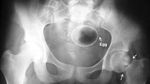

Pria yang satu ini mengincar cincin mahal seharga Rp 32 juta, untuk melamar kekasihnya. Karena ia tidak memiliki uang, akhirnya ia memutuskan untuk menelan cincin itu. Untungnya, pihak polisi dengan sigap menangkapnya, setelah alat metal detector di toko perhiasan itu berbunyi. Foto: Pool/Site